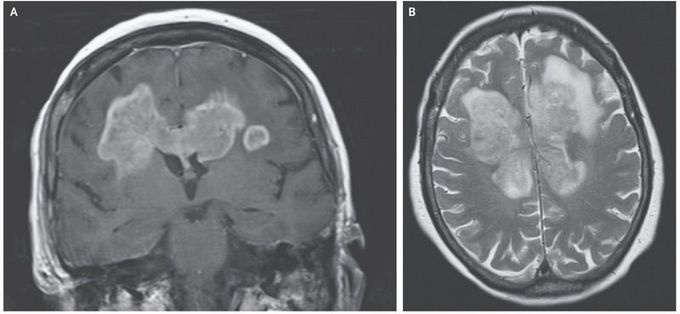

How up-to-date is the data around life expectancy. What is the longest documented glioblastoma survival. Butterfly glioblastoma bGBM refers to WHO grade IV gliomas that infiltrate the corpus callosum and spread to bilateral cerebral hemispheres.

Butterfly glioblastoma bGBM is a rare and sparsely described subgroup of glioblastoma with a bihemispheric tumour crossing the corpus callosum. I lost my father to cancer on 3rd June he had a glioblastoma multiforme stage IV not a lot is. It usually develops within a short time in middle-aged people.